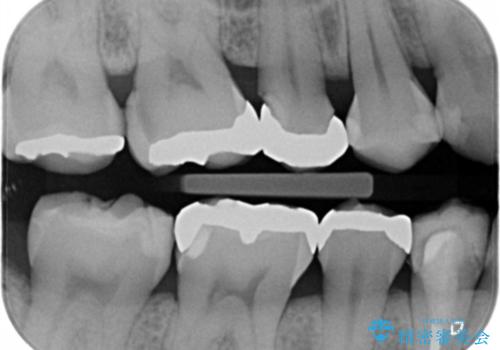

- 口を開けた時、銀の詰め物が目立つとのことで来院。

拡大鏡下で詰め物を外し、う蝕がない事を確認して、セラミック(e-maxインレー)で治療を行いました。

銀の詰め物は歯質との間の隙間ができやすく

虫歯の再発リスクが高いです。